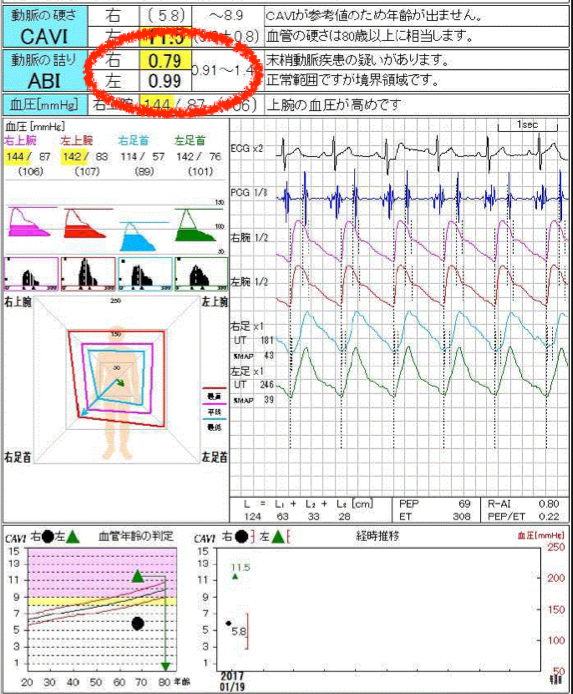

1、ABI検査 両手両足の血圧を同時に測定し下肢に十分な血液が流れているかどうかを判断します。(図1)

【図1】ABI検査 右足のABIが0.79に低下しています。